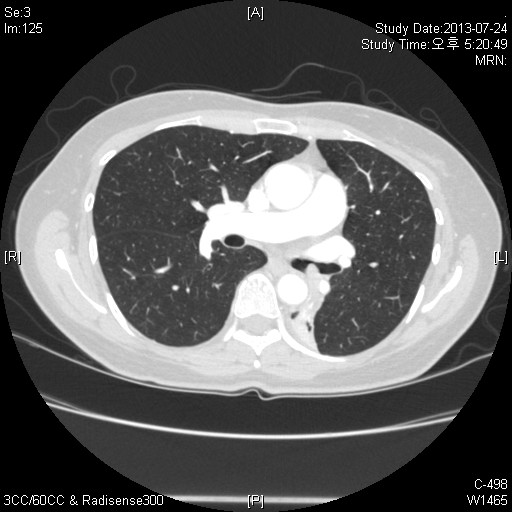

CXR»ó È®ÀÎÇÒ ¼ö ÀÖ´Â ¼Ò°ß, Á¤´äÀº LLL atelectasisÀÔ´Ï´Ù.

Chest PA»ó ½ÉÀå°ú Áß÷µÇ¾î »ï°¢Çü ¸ð¾çÀÇ À½¿µÀÌ º¸ÀÔ´Ï´Ù. ÁÂÃø Æó¹®ÀÌ Á» ³·¾ÆÁö°í ÁÂÇÏ¿± Æóµ¿¸ÆÀÌ Àß º¸ÀÌÁö ¾Ê´Â °æ¿ì°¡ ¸¹½À´Ï´Ù. lateral¿¡¼­´Â major fissure°¡ ÈĹæÀ¸·Î À̵¿ÇÒ ¶§ ÀǽÉÇÒ ¼ö ÀÖ°Ú½À´Ï´Ù.

CT¹× FOBÀÇ ¼Ò°ßÀ» º¸½Ã¸é LLL¸¦ obstructingÇϰí Lt main bronchus±îÁö protruding ÇÏ´Â mass°¡ °üÂûµË´Ï´Ù. FOB·Î biopsy»ó Carcinoid tumor°¡ Áø´ÜµÇ¾ú½À´Ï´Ù.

LLL atelectasis

Obstructing endobronchial tumor , Carcinoid tumor µÇ°Ú½À´Ï´Ù.